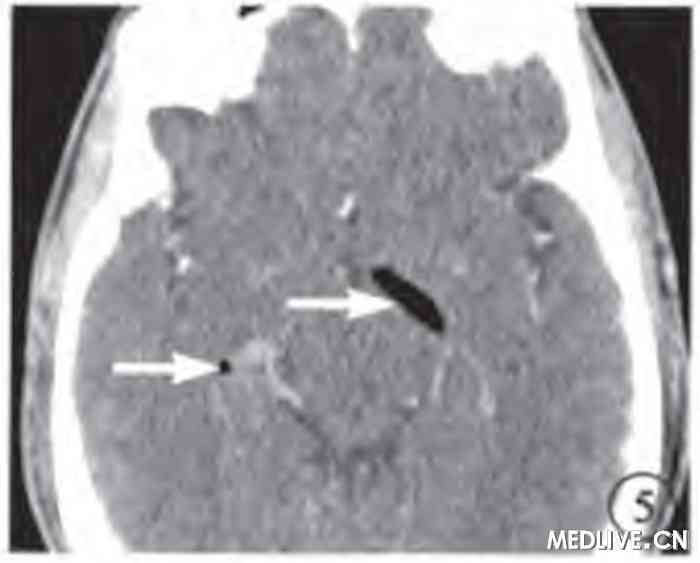

图1 玻璃体腔气体抽出手术前左眼CT横断面软组织窗像。玻璃体腔、视神经鞘内充满低密度气体 (白箭),视神经显示不淸,眼球前突。

图2 玻璃体腔气体抽出手术前左眼CT矢状面重建骨窗像。玻璃体腔、视神经鞘内、视交叉鞍上池内积气(白箭),视神经隐约显示。